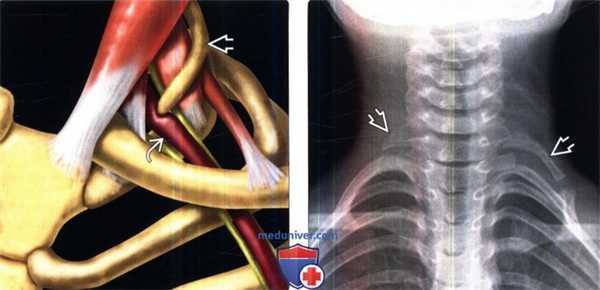

(Слева) На схеме показан сосудистый вариант синдрома верхней апертуры грудной клетки (СВАГК) с преимущественным сдавлением ПКА, вызванной удлиненным шейным ребром С7.

(Справа) На рентгенограмме в прямой проекции (пальпируемое образование в надключичной области слева, СВАГК) обнаружены шейные ребра у С7 позвонка с обеих сторон. Левое ребро С7 удлинено и образует аномальное сочленение с первым грудным ребром.